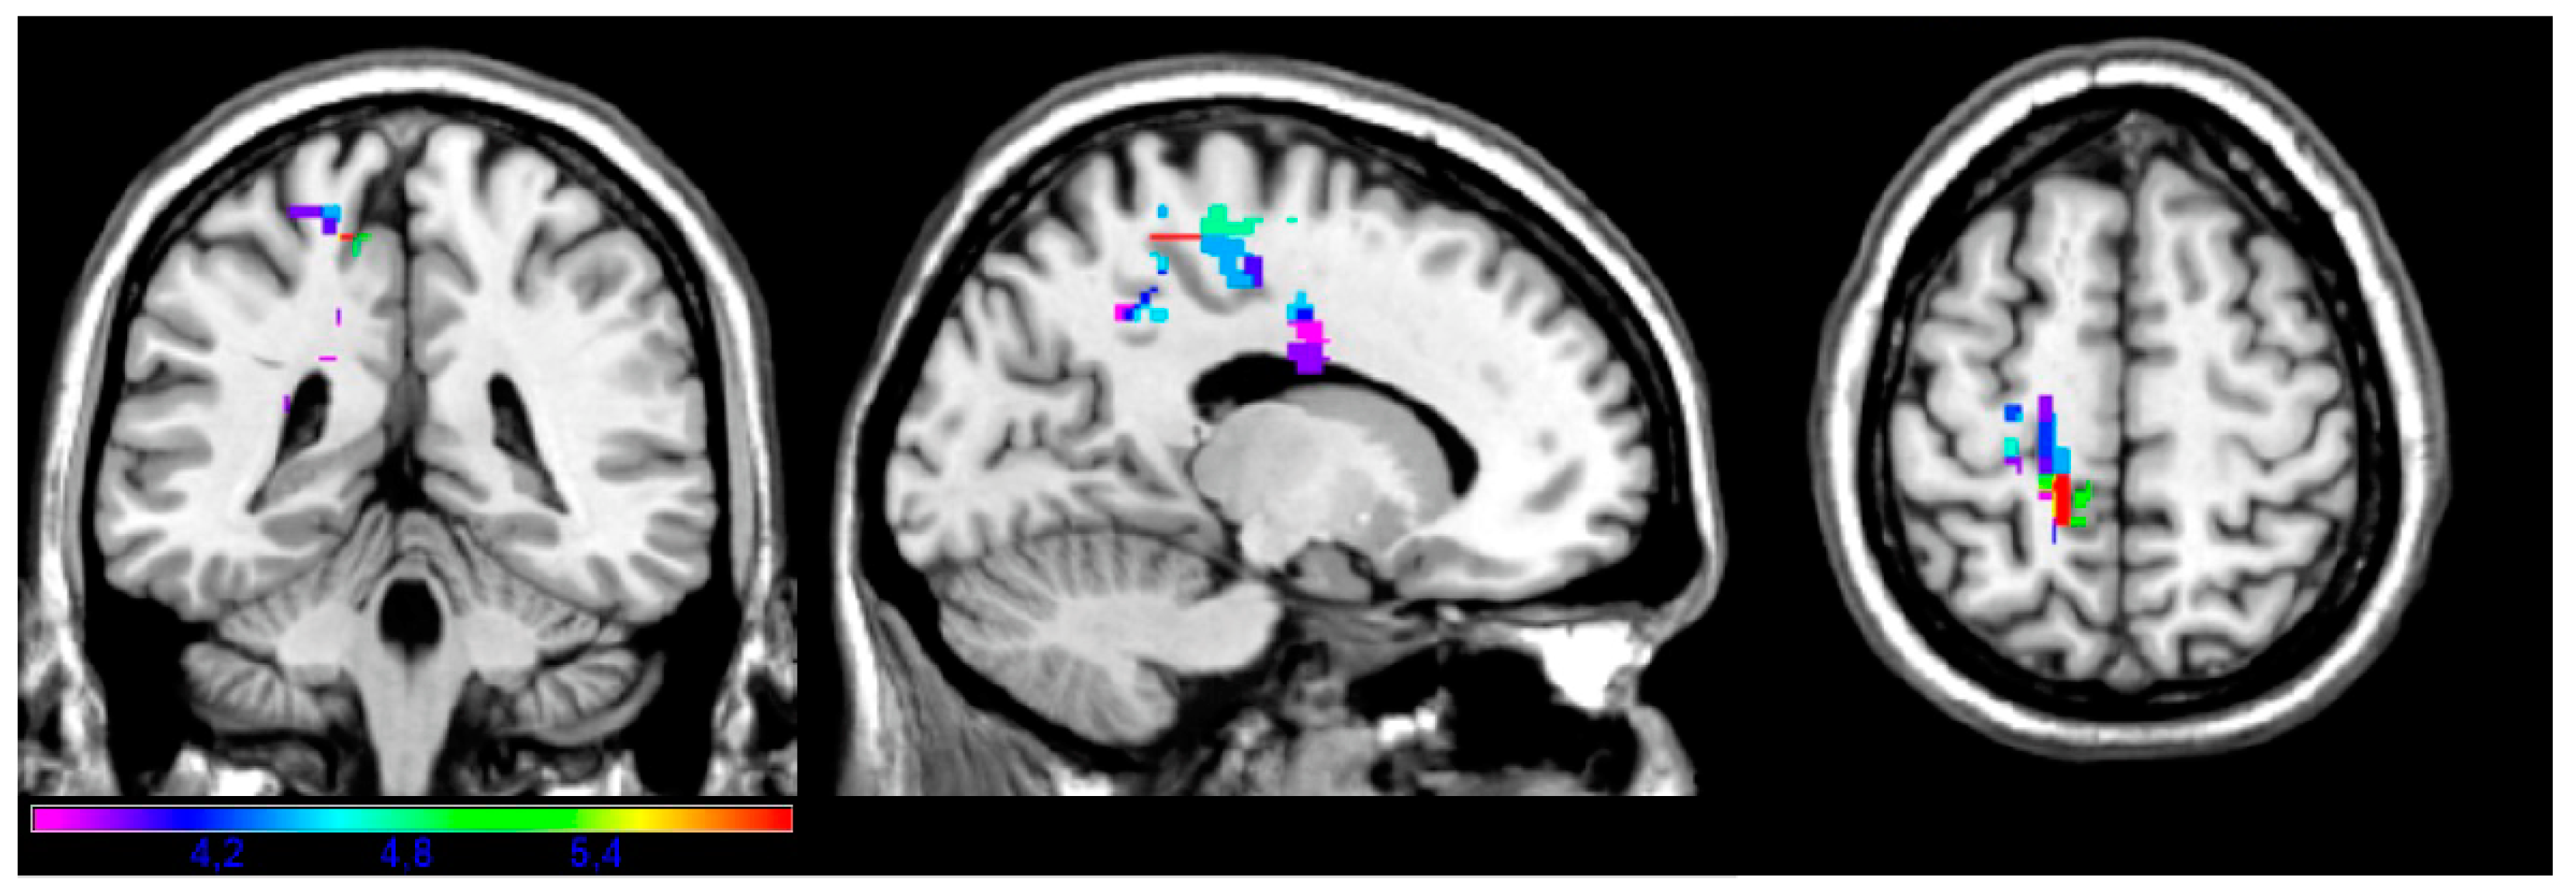

| Subtest | Volume | Px | Py | Pz | Min T | Max T |

|---|---|---|---|---|---|---|

| Facial | 88 | −50 | −34 | −20 | 3.67 | 5.58 |

| Upper limb | 68 | −72 | −16 | 2 | 3.57 | 5.1 |